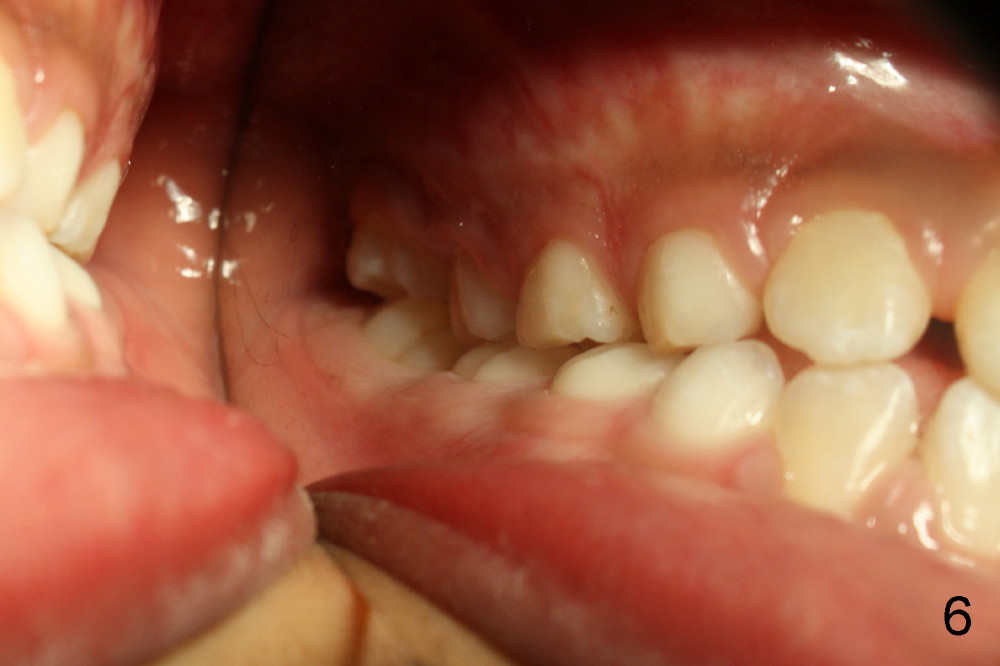

It appears that the chin deviates to the left (Fig.1). The lower dental midline also deviates (Fig.2,4). Profile shows possible bimaxillary protrusion (Fig.3). There is cross bite (deep overjet?) on the right side of the first permanent molars (Fig.5 mirror image), whereas the left posteriors apparently present edge-to-edge occlusion (Fig.6). Fig.7,8 are mirror views of the upper and lower arches, respectively. Panoramic X-ray demonstrates elongation of the right condyle (Fig.9). The right ramus appears to be longer than the left.